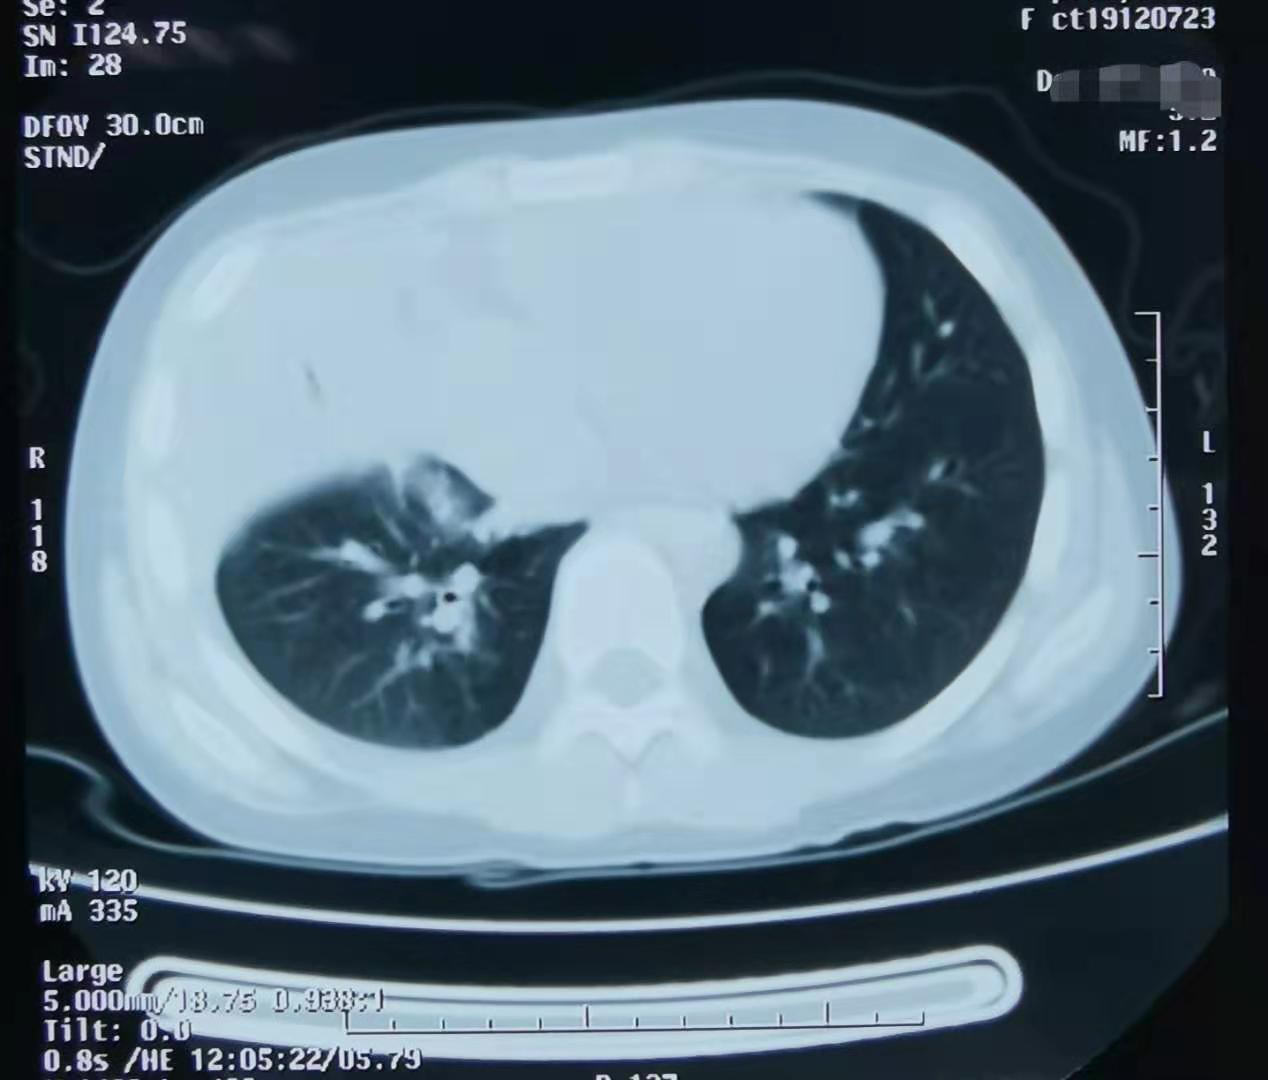

我一看检查结果,血象不高,中性粒细胞为主,C反应蛋白稍高,胸片右下肺一大片实变影,再一查体,右下肺呼吸音低,典型的支原体肺炎。我耐心的安慰家长。孩子的诊断没错,就是支原体肺炎,同时家长说明了为什么短期用药不见效的原因。

学龄期或学龄前期儿童有发热、咳嗽,肺部听诊无湿罗音,血常规白细胞不高或轻度升高或降低,中性粒细胞为主,CRP正常或增高,胸片可见大片实变影,临床需高度怀疑支原体肺炎。血清支原体抗体IgM滴度持续≥1:160或双份血清(间隔两周)抗体滴度上升4倍或下降为原来的1/4,一般认为是支原体感染。分子生物学检测支原体RNA阳性可诊断支原体感染。确诊的金标准是支原体培养阳性,但其培养时间长,故临床意义不大。